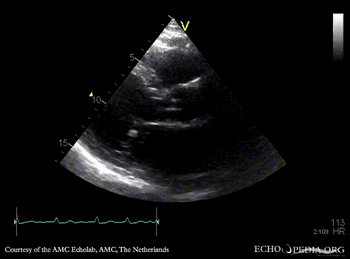

| A2CH | PLAX: Color Doppler, severe mitral regurgitation, excentric jet |